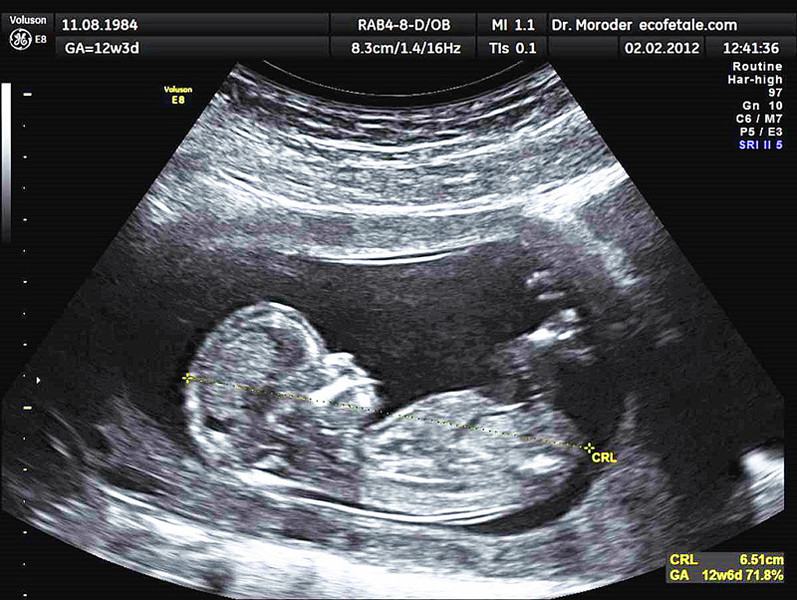

研究發現,男嬰「胎死腹中」比例較女嬰高出約1成。(photo by維基百科)

【台灣醒報記者李昀澔綜合報導】男嬰「胎死腹中」的比例,較女嬰高出近1成。英國艾希特大學團隊分析全球近3千萬名孕產婦就醫紀錄後發現,男嬰胎死腹中比例為千分之6.23,高於女性5.74,總人數多出約10萬。